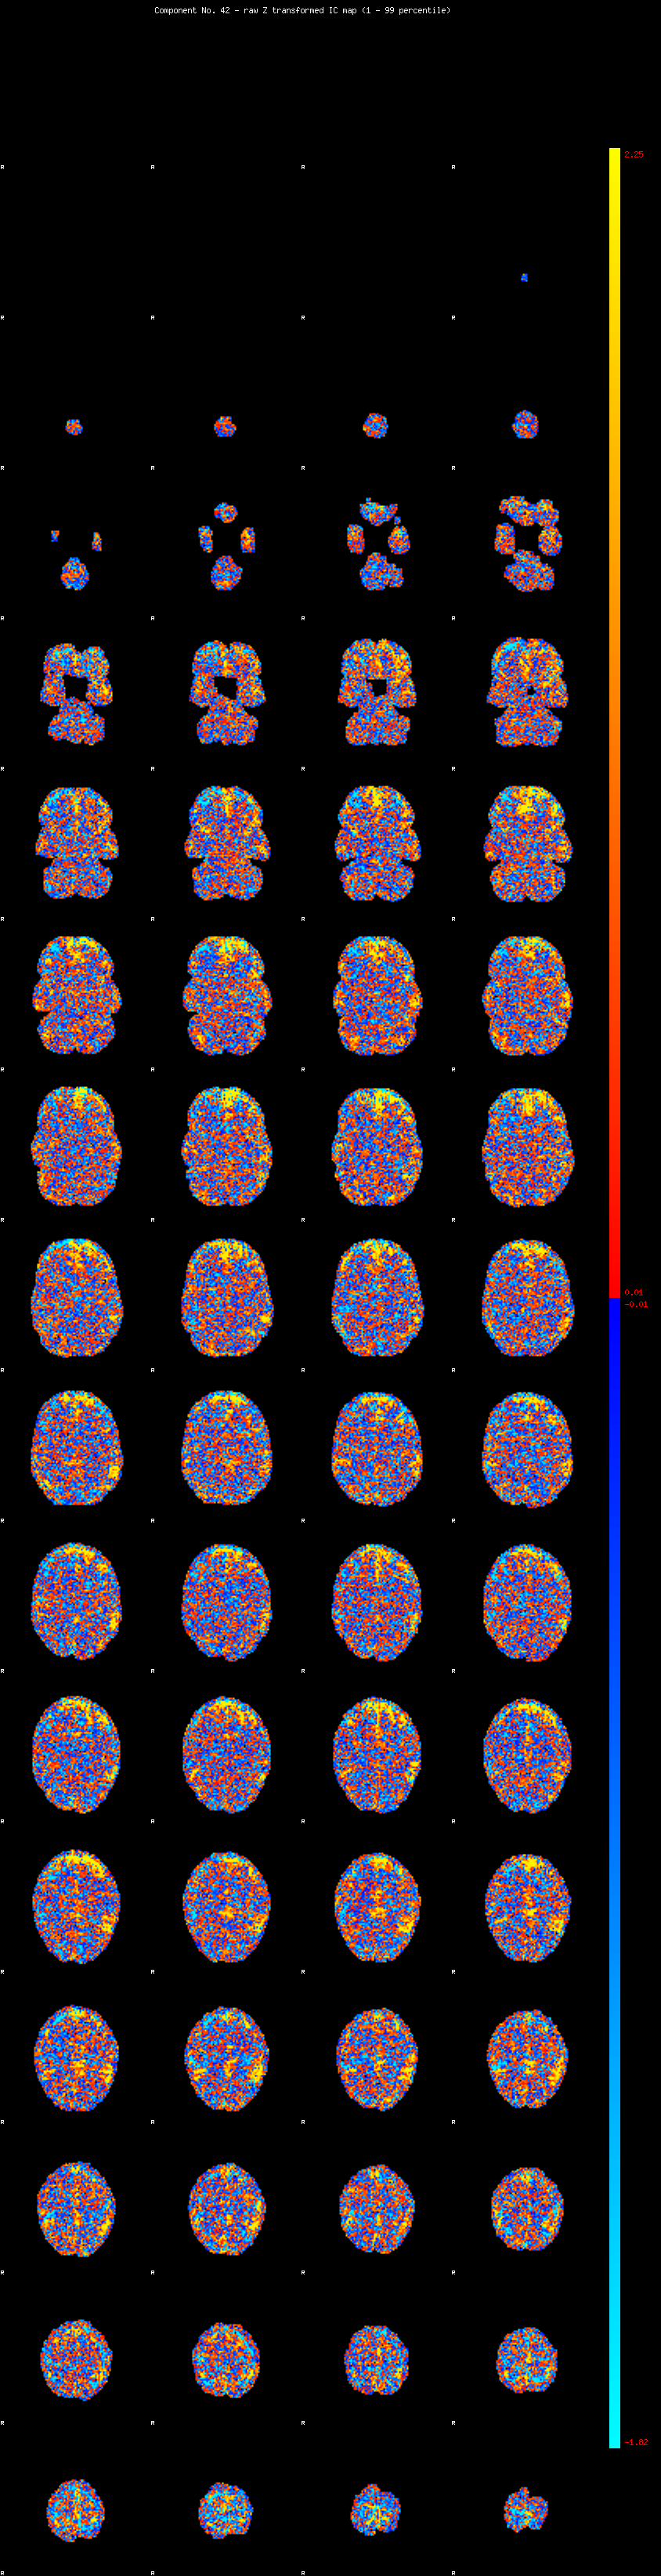

IC_42 Mixture Model fit

Means : -0.000000 3.372374 -2.981275

Vars : 1.000000 5.273786 1.402804

Prop. : 0.944711 0.044439 0.010850